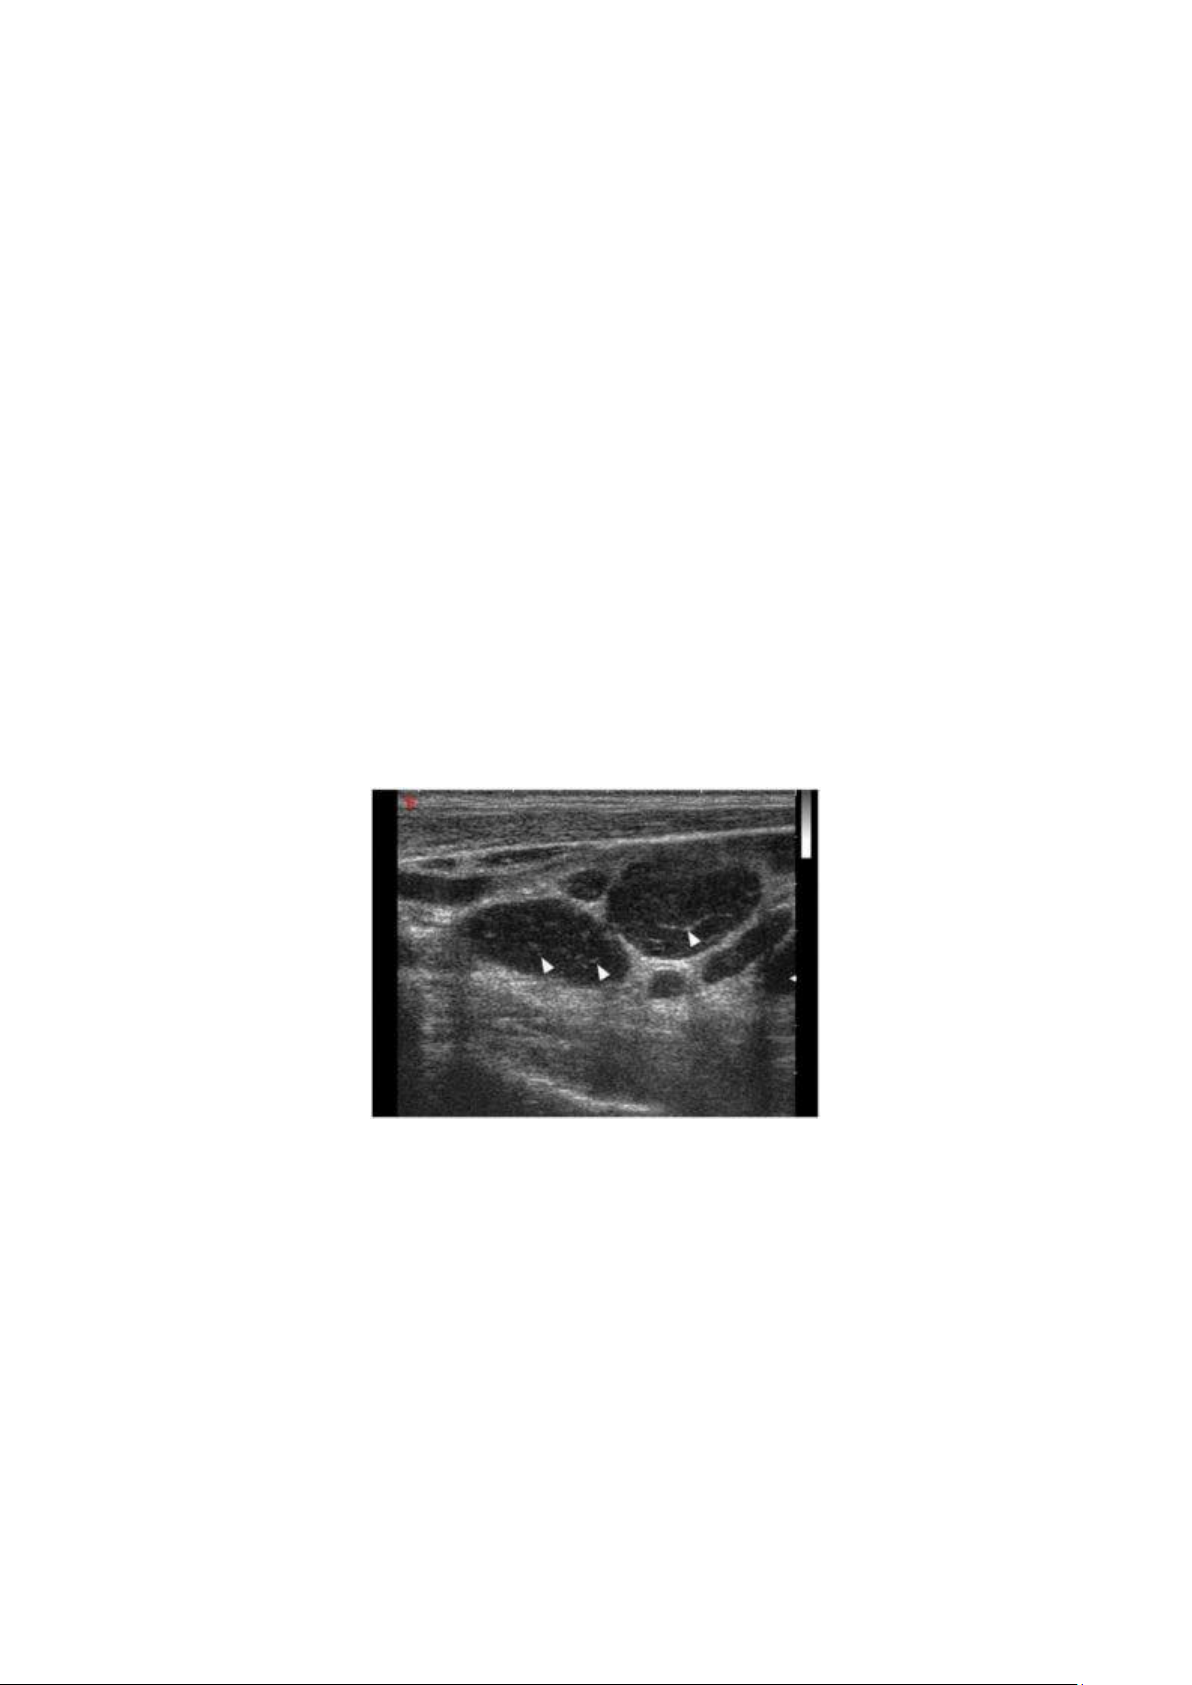

Hình 1.9. Siêu âm trắng đen cho thấy nhiều hạch ung thư có hồi âm kém. Đầu mũi tên chỉ

ra hình mắt lưới trong hạch, thường thấy trong hạch ung thư khi sử dụng đầu dò độ phân giải cao.